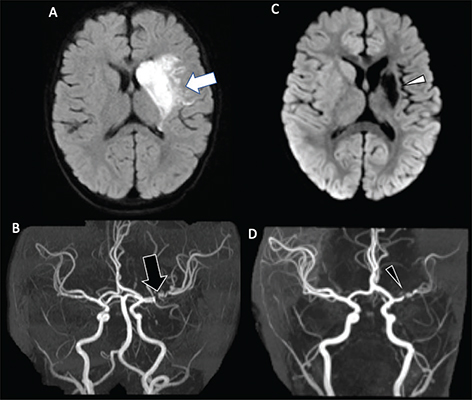

Fig 5

Figure 5. A 13-year-old previously healthy female who presented with new left-sided facial weakness. Diffusion weighted image (A) demonstrate acute infarcts in the right middle cerebral artery (MCA) territory (black arrows). Time-of-Flight MRA (B) shows stenosis of the proximal right M1 MCA segment (white arrowhead). Vessel wall imaging (C) demonstrates a cuff of enhancement at the stenosis (white arrow). Digital subtraction angiography (D) demonstrates a focal arterial irregularity and banding (black arrowhead) resulting in mild stenosis, compatible with focal arteriopathy of a likely inflammatory nature.